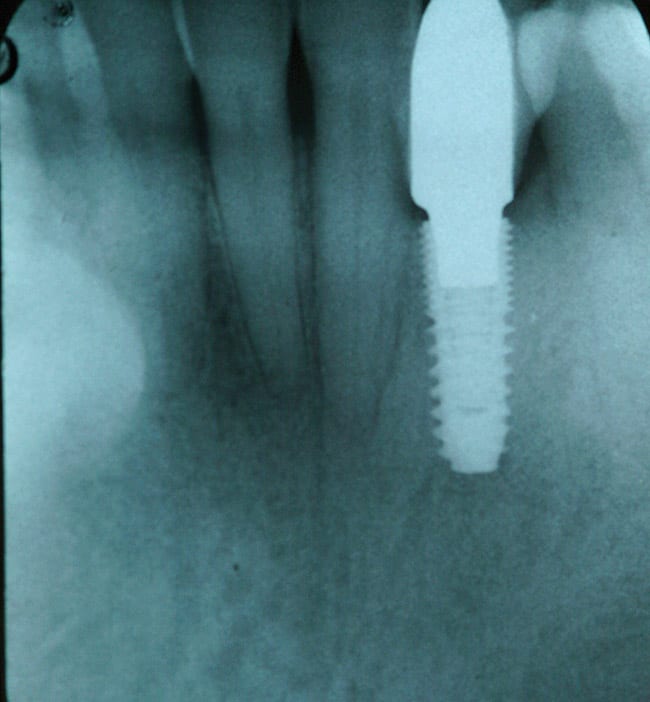

In another case showing the benefit of platform switching, a 40-year-old man presented with a missing lower right cuspid (Figure 7), which he reported was traumatically evulsed in a fistfight. He had limited finances and was unemployed for more than a year before he was able to afford to replace it. Since the two adjacent teeth were unrestored, he did not want to possibly damage them with crown abutments for a fixed bridge. He was offered a dental implant, restored with a single crown, and he accepted the treatment. Figure 8, a 2-year post-placement x-ray, shows no bone loss. A platform-switched abutment supports the crown on a 5.0-mm Hiossen implant with cervical microthreads at the top and placed with 60 newton centimeters torque. Figure 9 shows the final crown in place for 2 years, with optimal emergence profile and no tissue or bone loss. The microthreads have acted to stabilize the peri-implant marginal bone.